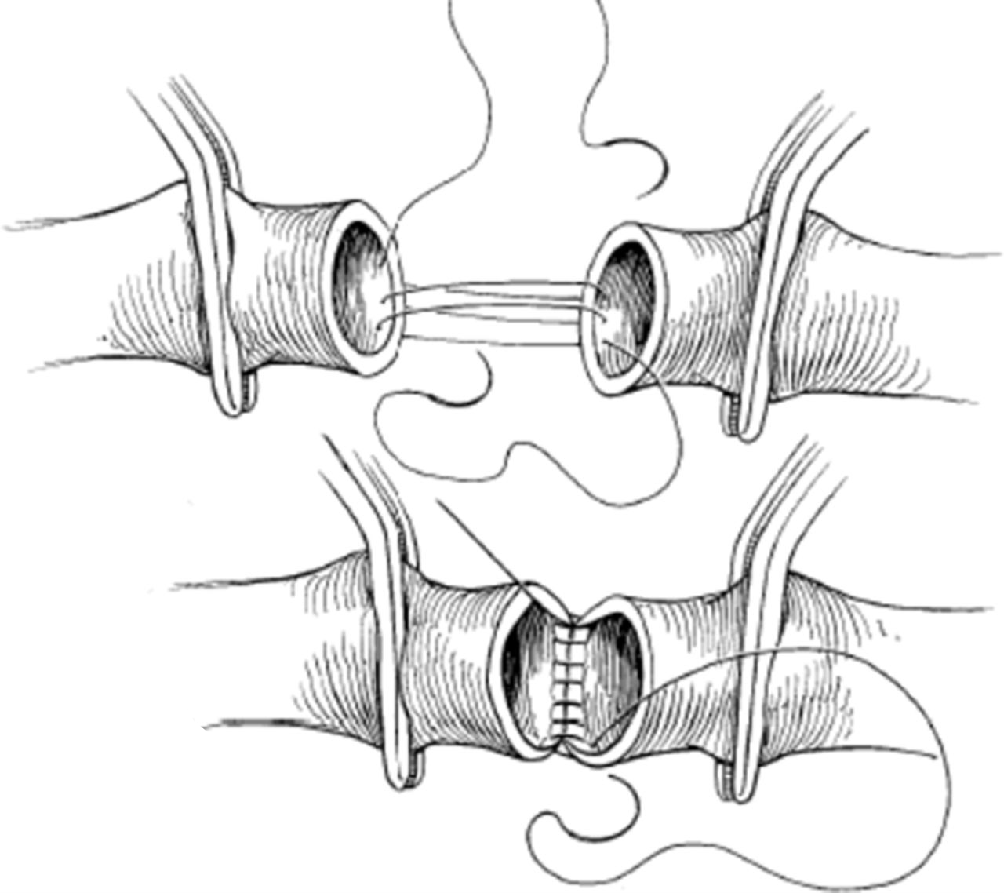

显微吻合技术突破显著提升远期通畅率。后壁优先缝合技术(posterior wall-first technique)的应用使吻合口狭窄率从传统方式的14.2%降至6.8%。其核心在于:

1. 足背动脉近端后壁与移植物180°连续缝合

2. 移植物内翻完成前壁缝合

3. 间断加固缝合关键受力点(尤其足背动脉管径<1.5mm时)